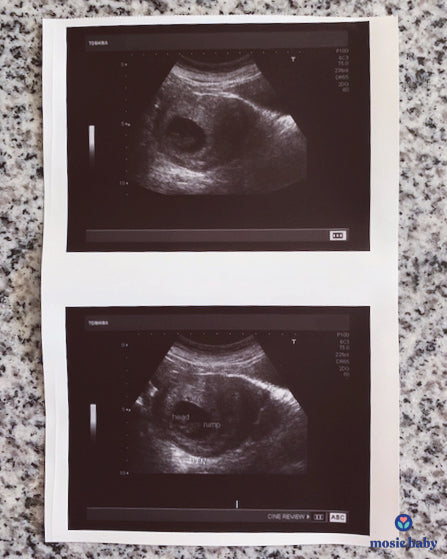

My husband and I wanted to start a family. We used a surrogate that is actually an old high school friend that volunteered. This has brought everyone so close. When starting our journey, Mosie came up and we knew it was the best. We were shocked that it worked on the first try. We are so excited to see our baby in January.

Here is a picture of our first sonogram! So grateful to Mosie baby!!!